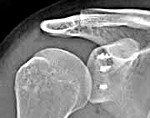

Установлено, что развитию данной патологии способствует повреждение суставной губы (повреждение Банкарта). Суставная губа является волокнисто-хрящевым образованием, которое прикрепляется к суставной впадине лопатки, делая вогнутую поверхность плечевого сустава более глубокой и препятствуя разобщению головки плеча и впадины лопатки при интенсивных движениях. Кроме того, у больных с привычными вывихами часто наблюдаются заднебоковые дефекты головки плечевой кости, обусловленные компрессионным переломом, не выявленным во время первичного травматического вывиха.